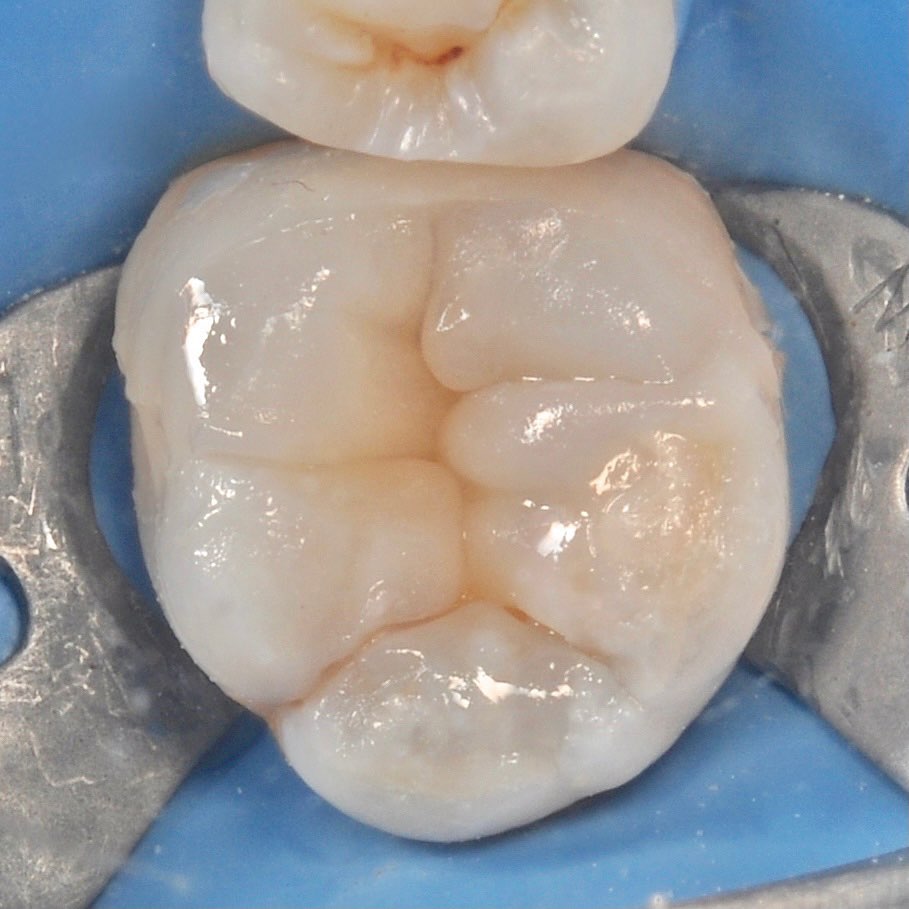

careful treatment of canals

Accurate determination of the geometry of the channels and their high-quality processing

strengthening the toot